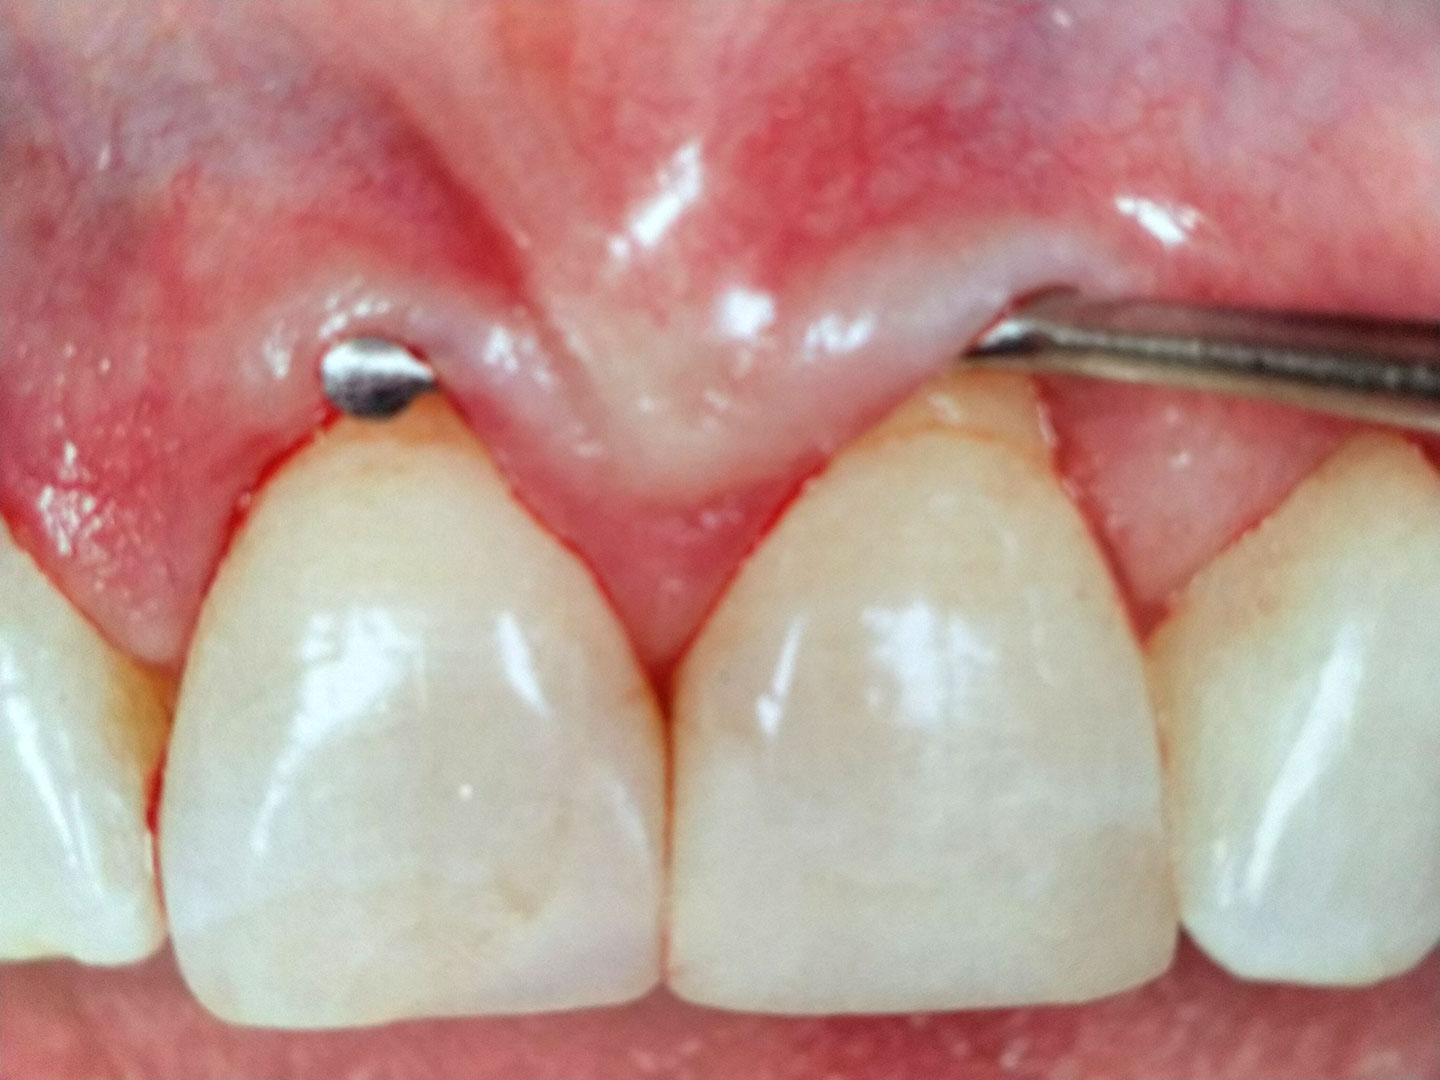

Bevor die Behandlung einer Parodontalerkrankung beginnen kann, ist es sinnvoll eine gründliche Anamnese durchzuführen. Bei dieser werden ein intraoraler und ein extraoraler Befund, sowie ein spezieller Parodontalbefund erhoben. Das Anfertigen von Röntgenbildern ist meist ebenso notwendig.

Hat sich eine Parodontits, also ein progressiver, entzündlicher Knochenabbau eingestellt, ist eine Parodontosetherapie notwendig. Je nach Befall und Situation geschieht diese durch eine geschlossene oder offene Kürettage. Bei der geschlossenen Kürettage wird eine intensive Reinigung und Desinfektion der Wurzeloberflächen unter örtlicher Betäubung durchgeführt, ohne dass das Zahnfleisch abgeklappt werden muss. Die offene Kürettage bedingt das Abklappen des Zahnfleisches von den befallenen Zähnen, damit die Wurzeloberflächen unter Sicht gereinigt und Entzündungsgewebe entfernt werden kann.